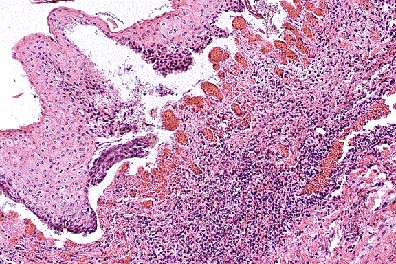

Lymphoplasmacytic periglomerular inflammation in the kidney of a 6-month-old pig. (HE, 200X, 56K)

The capsular surface is irregular due to multifocal interstitial fibrosis and accompanying infiltrates of lymphocytes and histiocyte. Adjacent tubules are frequently lined by flattened epithelium or by tall, lightly basophilic epithelium (regenerative). Occasional tubules are dilated and contain numerous neutrophils. Inflammation is principally confined to the cortex. The epithelial lining of the renal pelvis is often vacuolated.

Lesions indicate two separate processes: interstitial nephritis and pyelonephritis. The interstitial component is similar to that described for swine infected with Leptospira interrogans. Numerous intratubular and few interstitial leptospires are seen on immunohistochemical stains. The cause of the ascending tubular infection was not determined (no fresh tissue received).

AFIP Diagnosis: Kidney: Nephritis, tubulointerstitial, chronic-active, diffuse, moderate, breed not specified, porcine.

Conference Note: The Warthin-Starry method demonstrated numerous, delicate, 5 to 20 m long spirochetes consistent with Leptospira sp. within the proximal renal tubules. The single diagnosis of tubulointerstitial nephritis was chosen because the participants were not certain that two separate pathologic processes were involved.